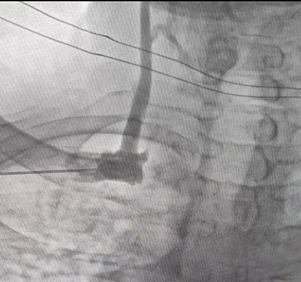

▲左侧有透析管,行右侧造影图

该患者上肢血管,一侧造瘘,一侧闭塞,无法植入传统经静脉ICD。只有走植入S-ICD这一条路了,S-ICD是在心脏性猝死预防领域取得革命性突破的新技术,它能够提供与经静脉ICD相同的预防心脏骤停的治疗。S-ICD的整个系统只植入于皮下,不直接接触心脏和血管,能够彻底杜绝可能的血管及心脏损伤、减少潜在的血液系统感染风险,保留静脉通路,避免经静脉导线植入拔除的一系列并发症,如电极断裂、囊袋感染、心肌穿孔的发生,做到了真正的“无触心脏,保驾护航”。而最新的“二切口”植入技术,能进一步减少创伤,给患者带来更好的术后体验。